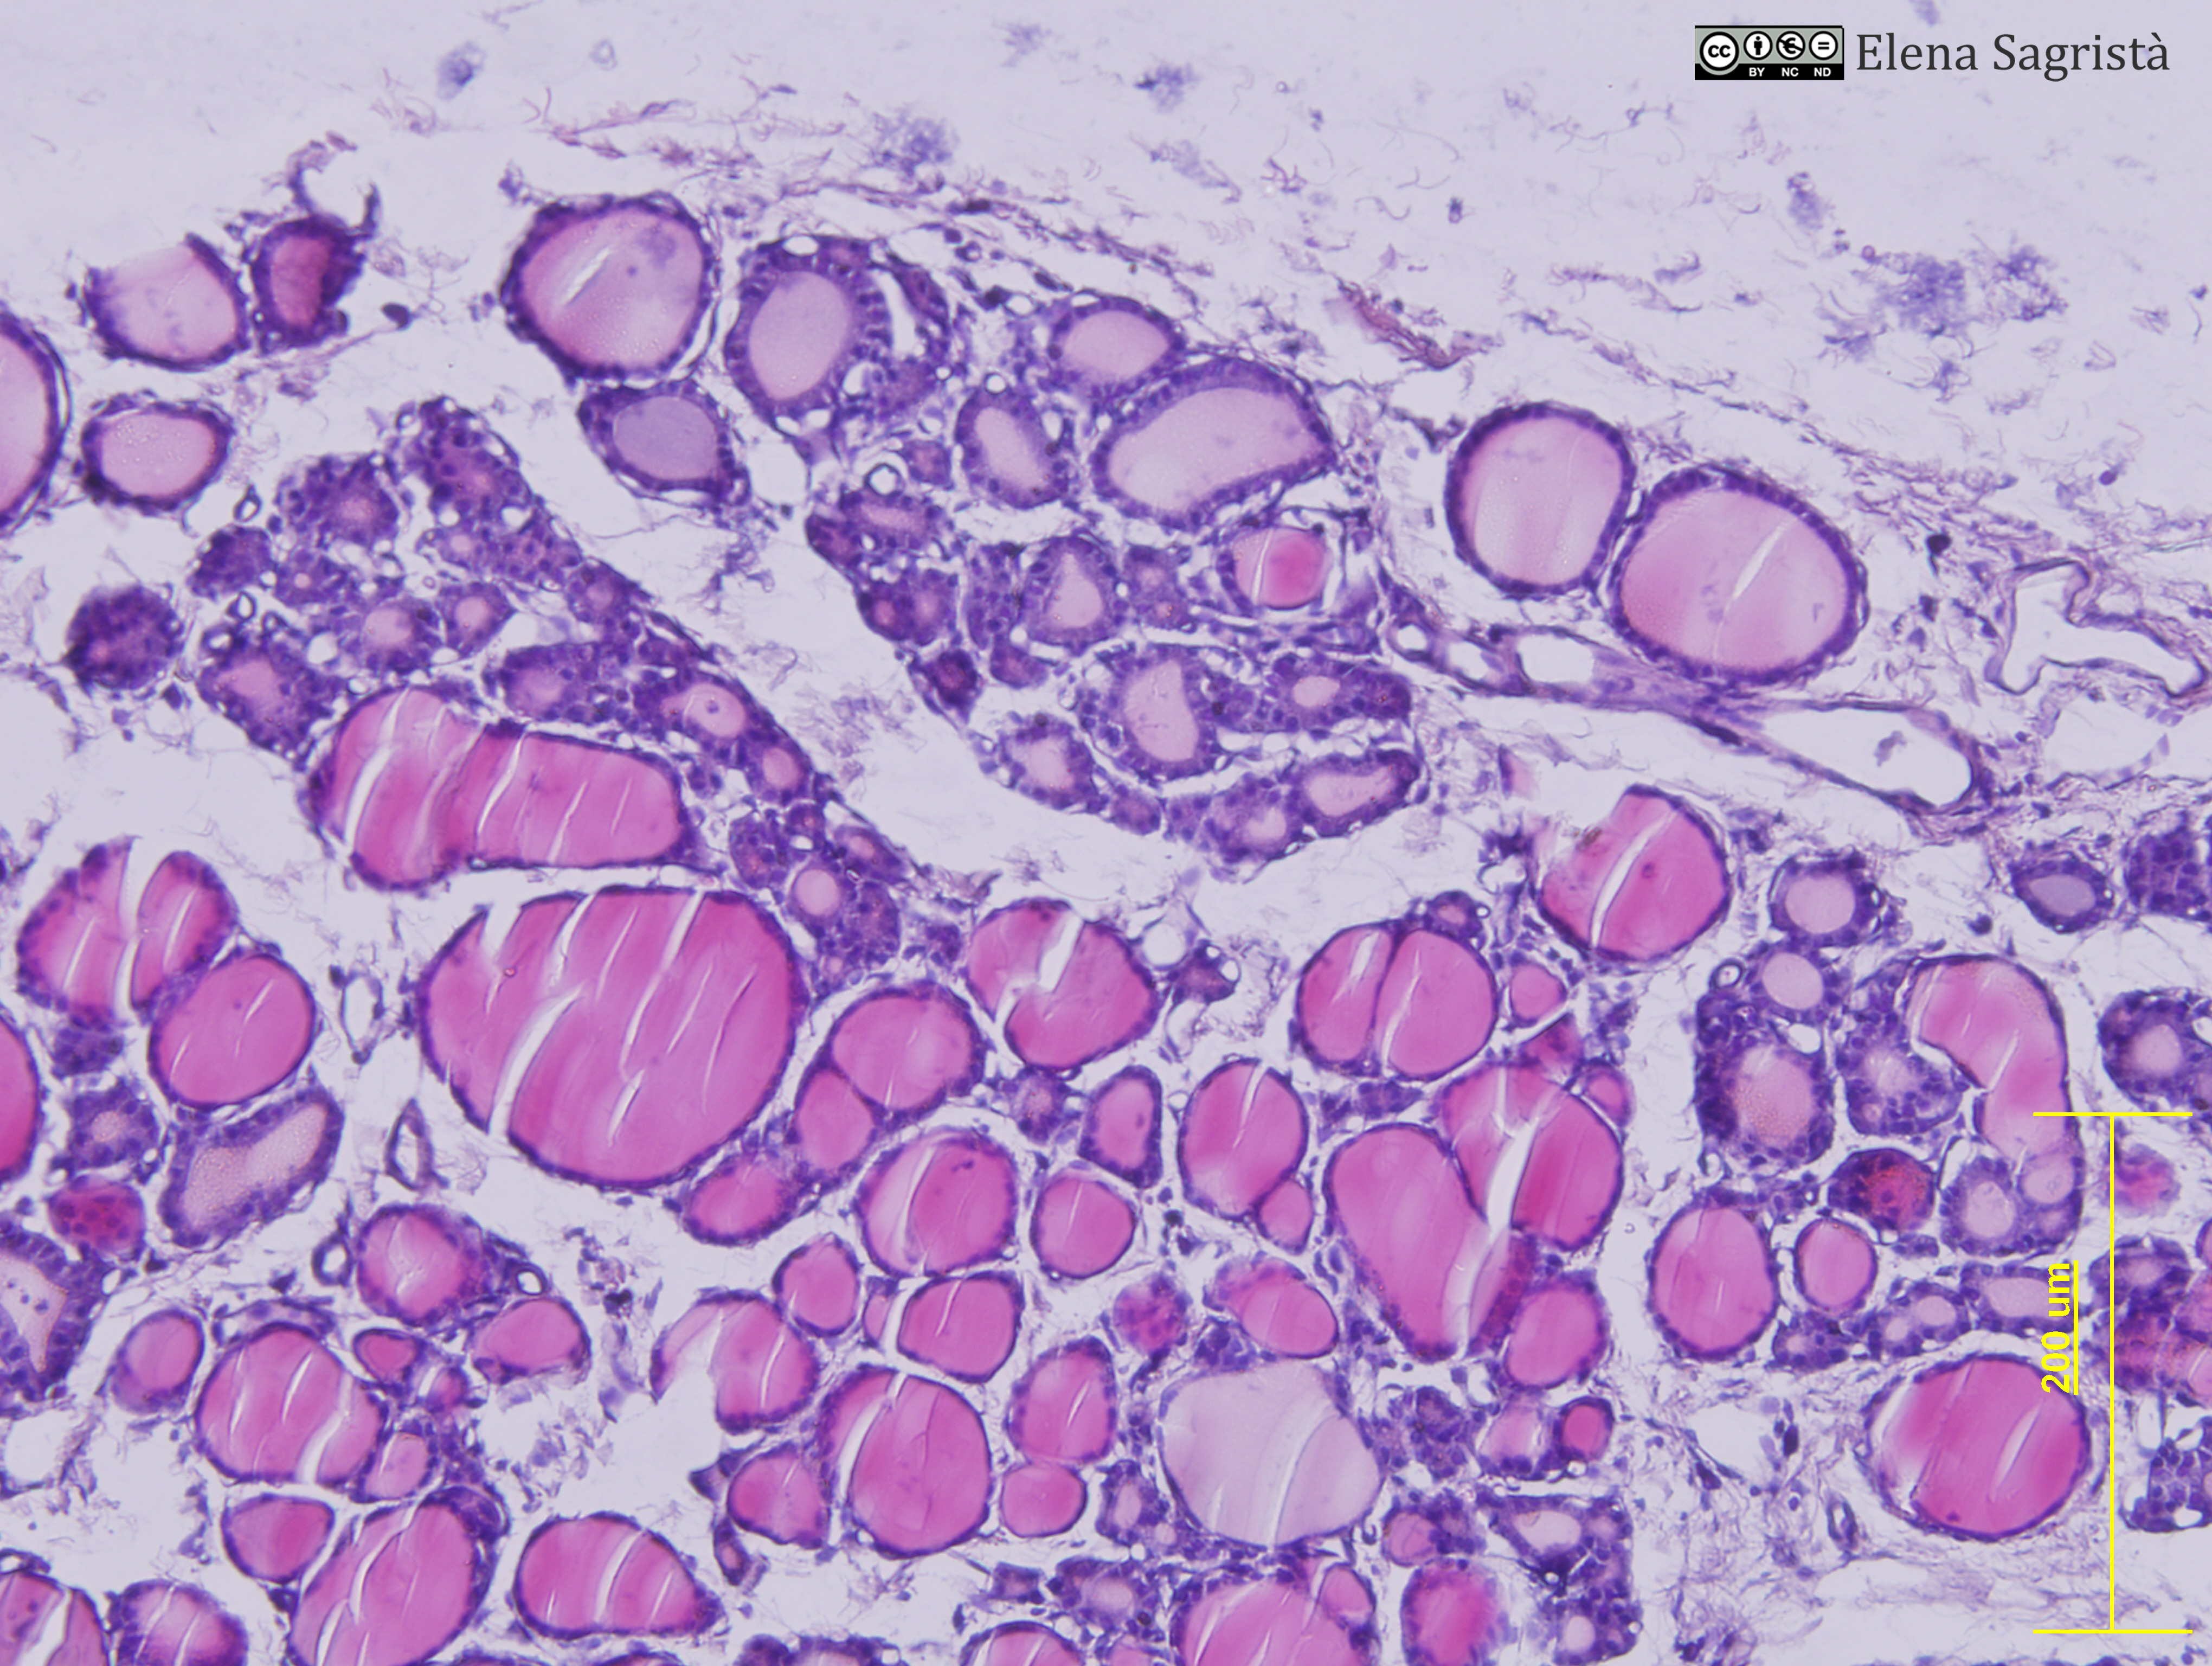

Histologia imatges: 25 Tiroide

Imatges de preparacions histològiques de Tiroide. Microscòpia òptica.